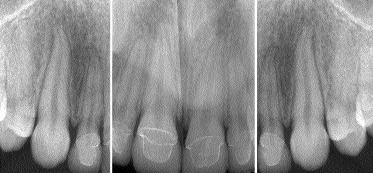

FIGURE 9--Radiographic confirmation of crown to root adaptation.

The “magic” combination of meticulous treatment-planning together with special chemistry between patient, dental team, and laboratory technician usually exists in our most successful cases. This article illustrates how early recognition of a dental problem and a systematic plan for its correction has enabled this 17-year-old patient to bloom and be ready to take on the world.